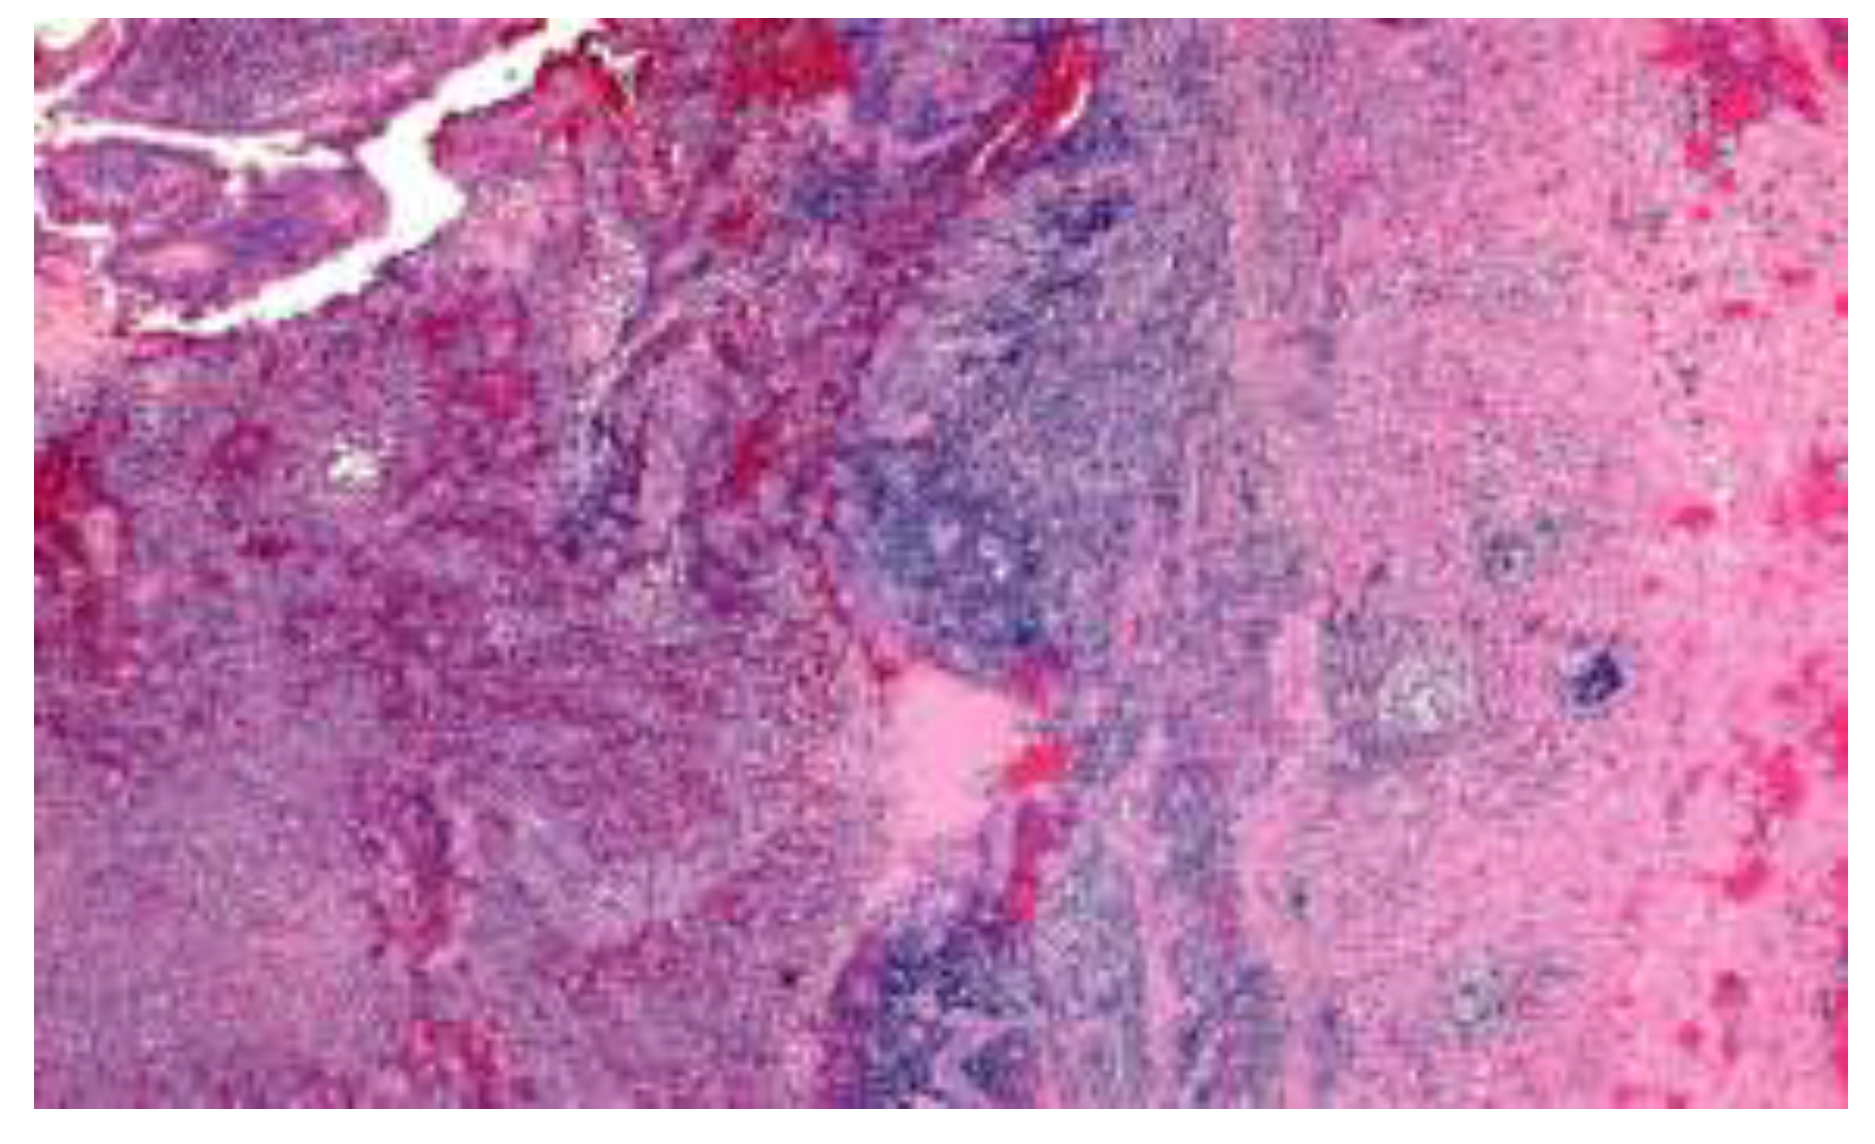

- the focal or the discontinuous inflammation of the mucosa with or without the lengthening and distortion of the crypts, with predomination of histiocytes and lymphocytes in the inflammatory infiltrate.

- epithelioid granulomas.

- the presence of lymphoid aggregates at the border of the muscularis propria and subserosa, associated with the infiltration of the muscular layer by mononuclear leukocytes in most cases [30].